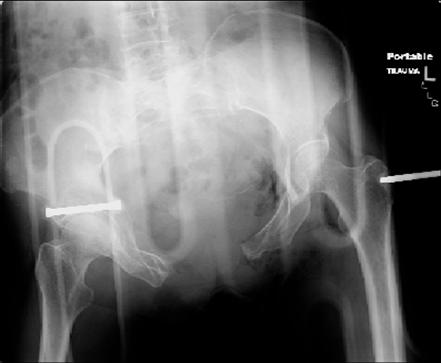

attached are images of a 70 year old female after peds versus car. her own car ran her over.

injuries are limited to the pelvis. left rami open and visible in a 10cm vertical laceration just lateral to left labia majora. wound is grossly clean. no vaginal and no urinary issues. CT scan shows widening of both SI joints anteriorly but I think this is vertically stable pattern.

pt treated that night with I/D and supra-acetabular frame to close the ring. consideration was given for SI screws bilateraly, but given time of night and other factors decision made not to proceed.